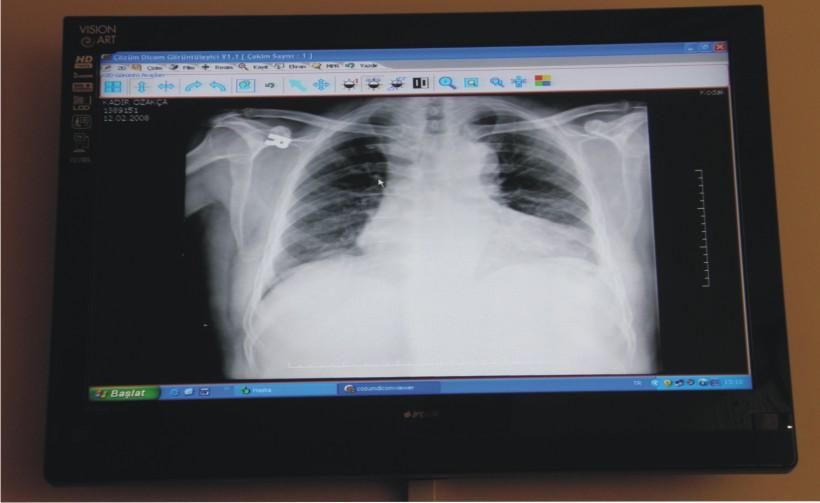

Görüntülerin daha net izlenebilmesi için Medikal Monitörler kullanılıyor.

Work Station ile birlikte yüksek çözünürlükteki görüntülerin net görüntülenebilmesi, tanı ve teşhisle-rin sağlıklı yapılabilmesi için tasarlanmış Medikal Monitörler kullanılıyor.

Panaromik görüntüler, çözünürlükleri bozulmadan büyütülerek ayrıntılı bilgiler elde ediliyor.

Sayısal görüntüler üzerinde işlem ve ölçüm yapılabiliyor. Görüntüler ve raporların her an, her yerde (tüm iş istasyonları üzerinden sorgulama yapılarak) ulaşılabilir olmasına ve görüntü işleme ve ölçüm (mesafe, açı, uzunluk, yoğunluk) yapılabilmesine olanak sağlıyor.

Radyoloji uzmanlarının tanı süreçlerinin sonuçlanmasında ve doğruluğunda en büyük yardımcı etken Çözüm PACS oluyor [sayısal olarak elde edilen panoromik görüntüler, çözünürlük bozulmadan büyütülüp, belirli bir noktaya odaklanarak, daha detaylı bilgiler elde ediliyor, görüntülerin herhangi bir yerine yazı veya şekil yerleştirmesi ve seçilen görüntünün fare kontrolünde yer değiştirmesi (pan) ve tam ekran incelemesi mümkün oluyor.] İncelenen görüntüler istenildiğinde DICOM yazıcılara gönderilerek film olarak basılabiliyor.